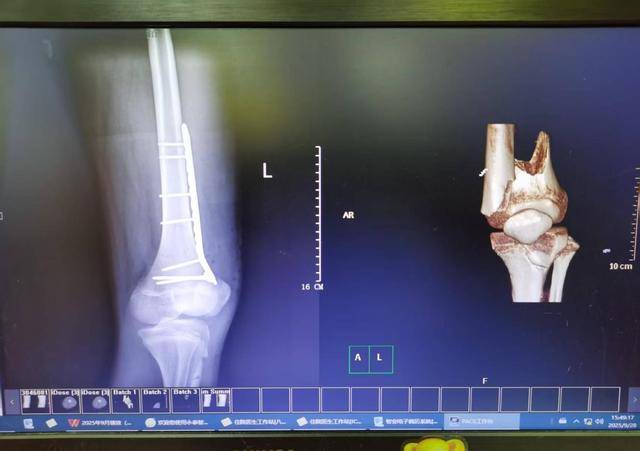

(术后术前对比)

在董洁的带领下,由何芳清、何迎波等主治医师组成的手术团队,为患者实施“左股骨远端骨折开放复位钢板内固定术”。手术中,团队配合默契,展现出高超的专业技术,在有限的操作空间内精准复位每一处骨折块,并完成内固定安置,全程完好地保护了骨骺结构,实现骨折修复与生长功能保全双重目标。术后,经过医护团队的精心治疗和护理,患者恢复顺利,左膝关节功能得到良好保留,于10月初康复出院。